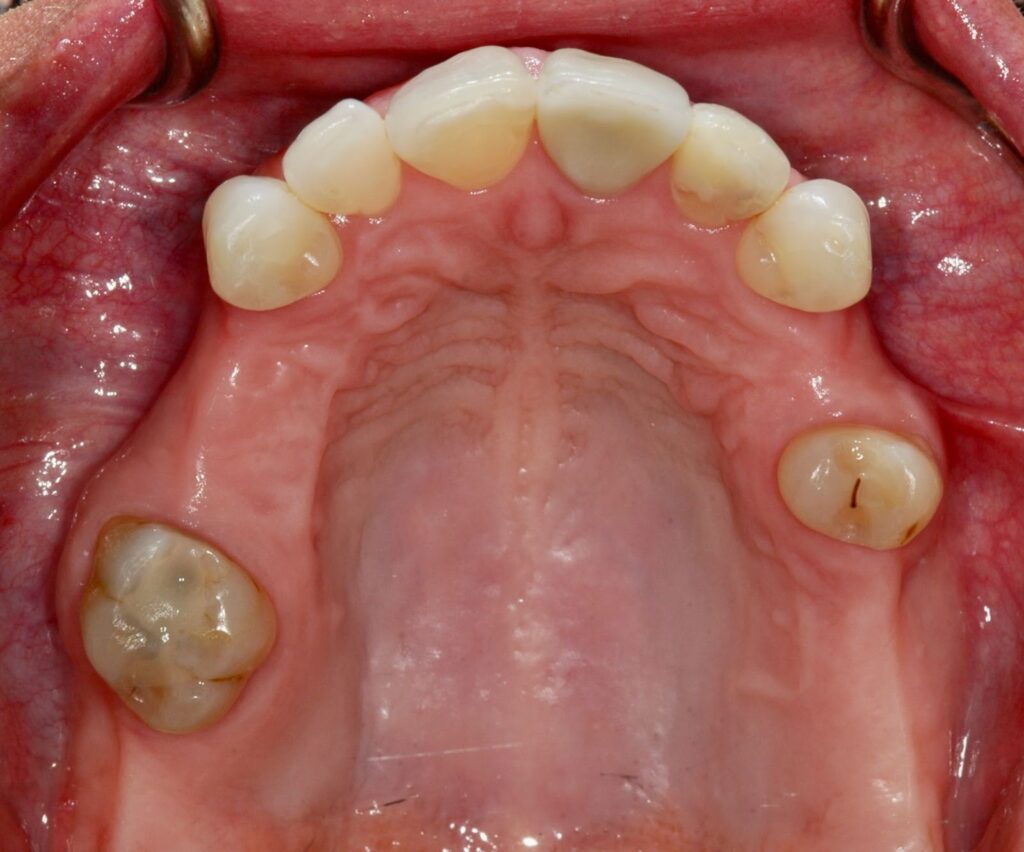

2. Removable Partial Dentures

Partial dentures replace several missing teeth and attach to the remaining natural teeth using clasps.

Best for: Patients who still have some healthy natural teeth.

Comfort level: Good when properly designed, though clasps may take time to get used to. Material: Metal framework with acrylic.